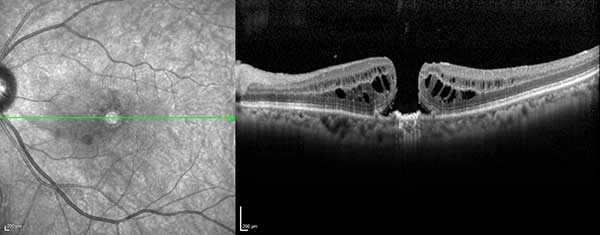

“The case studies include real life examples of macular disease and provide the patient history, OCT and fundus examination results”, explains Christopher Mody, Director of Clinical Services. “They are designed to enhance and test the diagnostic skills of optometrists and dispensing opticians who must diagnose and manage each case correctly and then compare their answers to the feedback from the subject expert.”